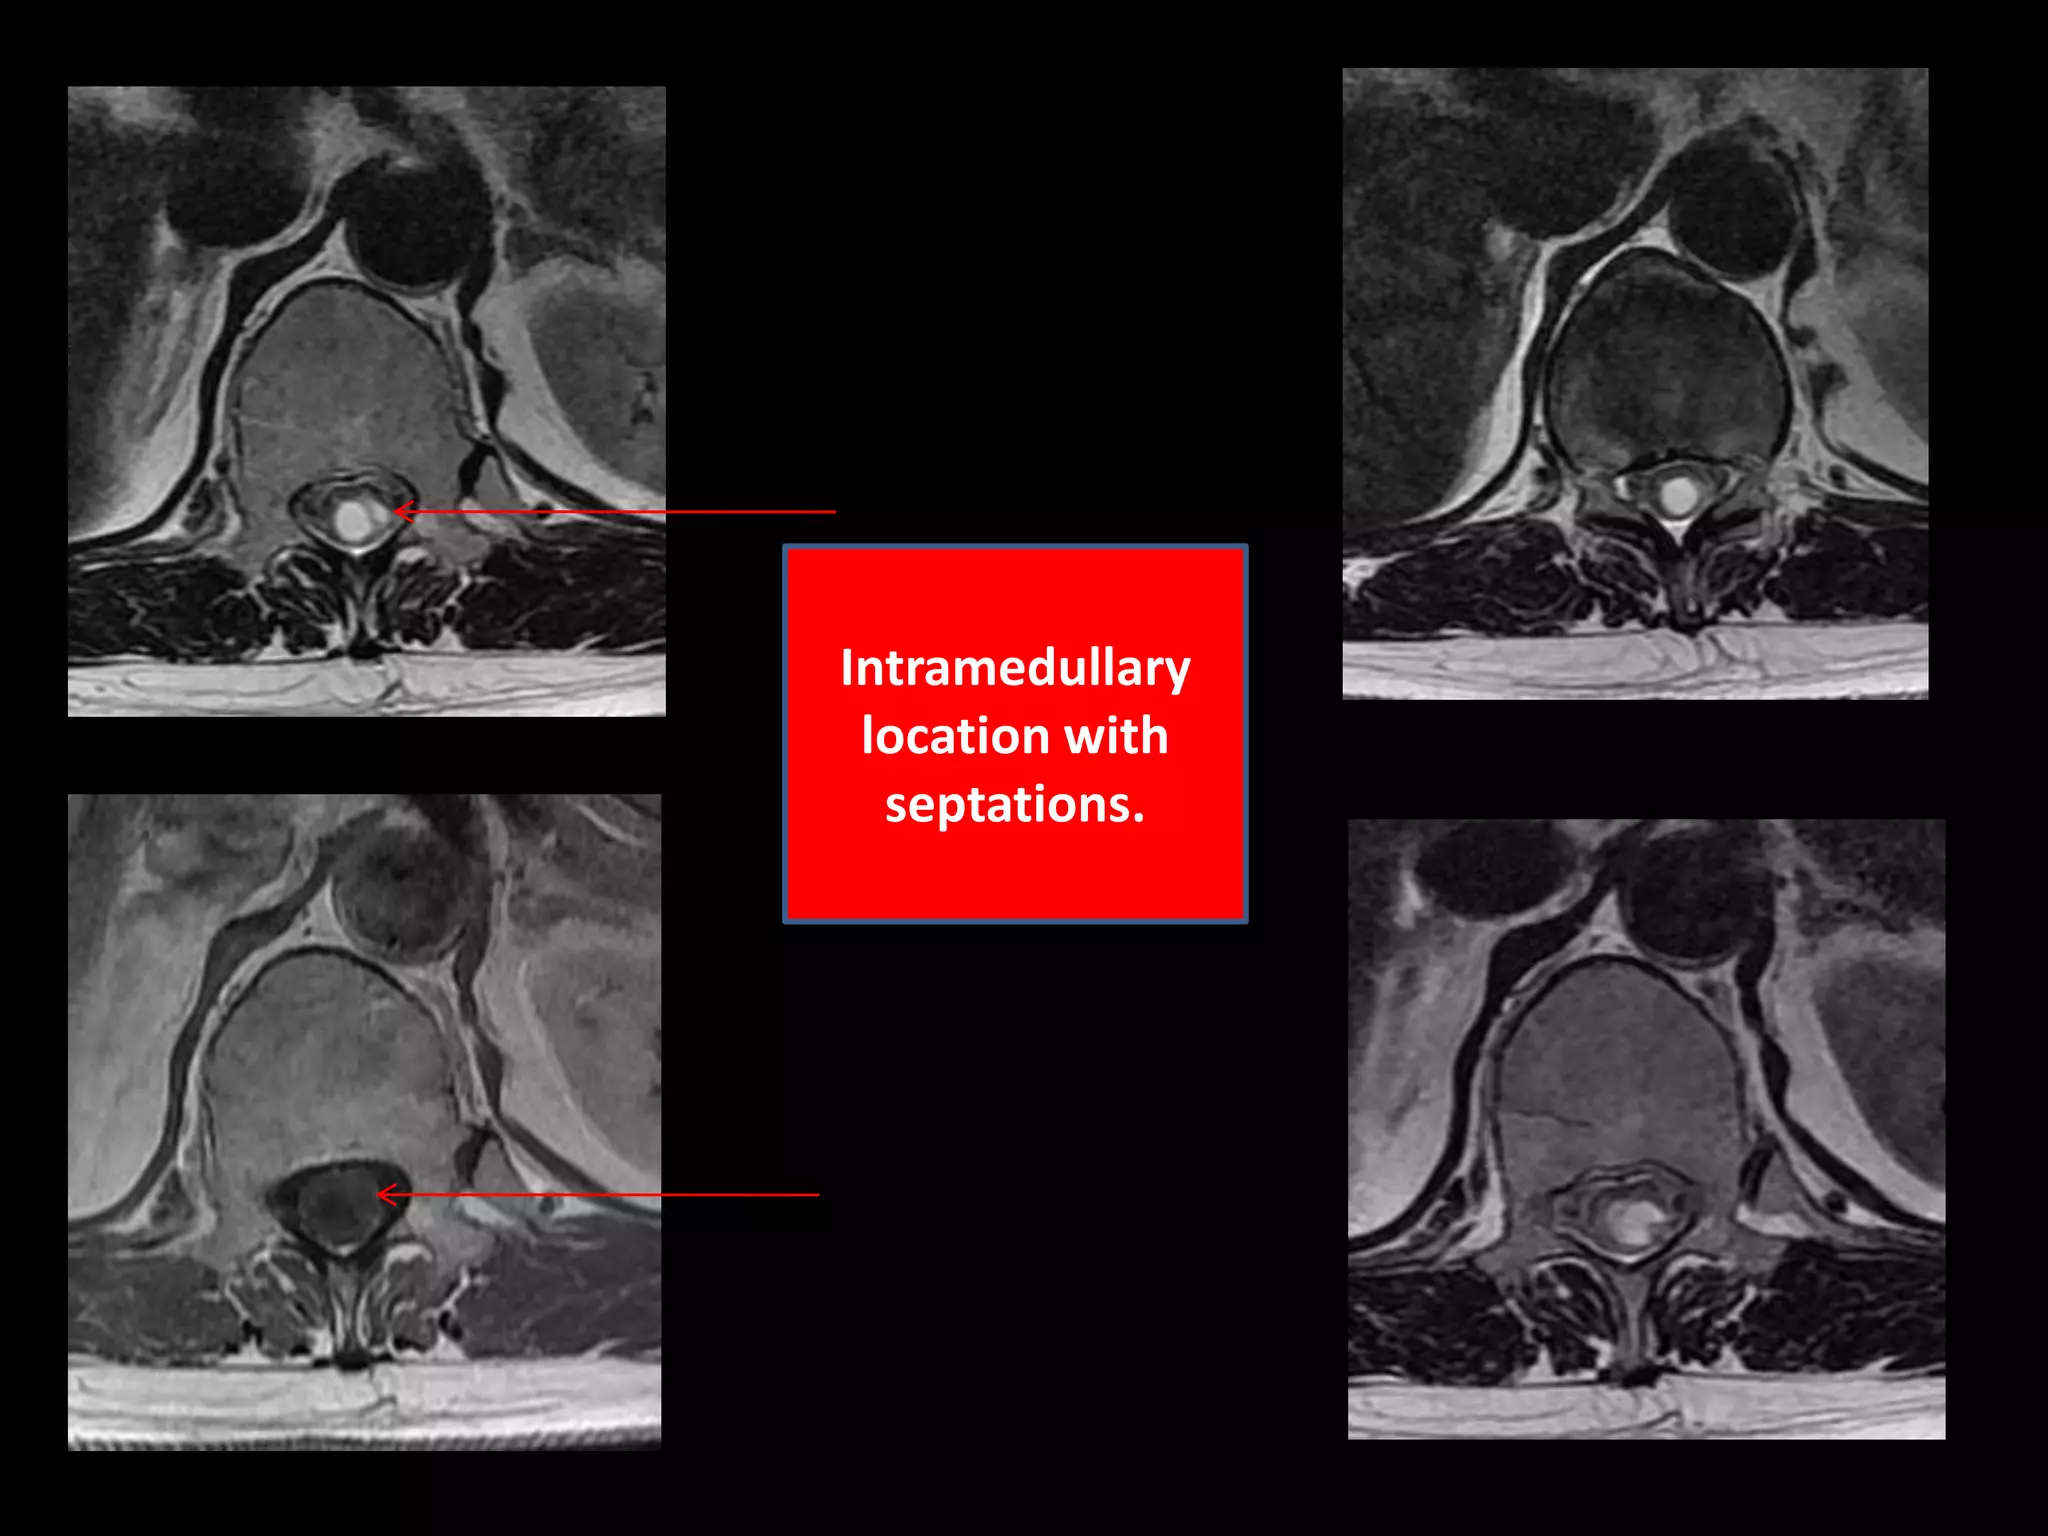

Case 158 Year old female with sensory and motor complaints pertaining to lower extremity with worsening for last one year. MR Images – Intramedullary cystic lesion ( size 28mmx 08mmx 08mm ) with septations and solitary intensely enhancing tumor nodule is appreciated in the lower dorsal region.                                  Important negative findings are :No cap sign appreciated. No signal voids appreciated .No associated syrinx .No Intratumoral cysts /Peritumoral cysts .No pathological enhancement elsewhere in the tumor.

Intramedullary location with septations.

Case 158 Yearold female with sensory and motor complaints pertaining to lower extremity with worsening for last one year. MR Images – Intramedullary cystic lesion ( size 28mmx 08mmx 08mm ) with septations and solitary intensely enhancing tumor nodule is appreciated in the lower dorsal region. Important negative findings are :No cap sign appreciated. No signal voids appreciated .No associated syrinx .No Intratumoral cysts /Peritumoral cysts .No pathological enhancement elsewhere in the tumor.